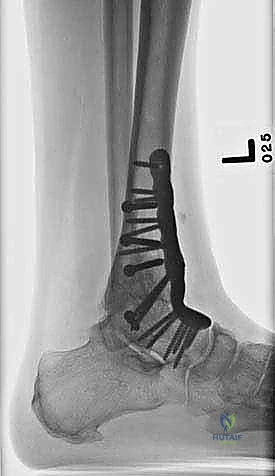

- الأشعة السينية أثناء الوقوف (Weight-bearing X-rays): هي الفحص الذهبي والأهم. يجب أن تؤخذ الأشعة والمريض واقف لتحمل الوزن. تظهر الأشعة تضيق المسافة المفصلية (دليل على فقدان الغضروف)، وجود نتوءات عظمية، تصلب العظم، وأي انحراف في محور المفصل.

لماذا المدخل الأمامي (Anterior Approach)؟

- تثبيت ميكانيكي حيوي أقوى: يتيح المدخل الأمامي وضع شريحة معدنية (Anterior Plate) على الجانب الأمامي للمفصل. من الناحية الميكانيكية الحيوية (Biomechanics)، يعتبر الجانب الأمامي هو "جانب الشد" (Tension side) أثناء المشي. وضع الشريحة هنا يوفر تثبيتاً فائق القوة ويقلل من معدلات عدم الالتئام.

- التخطيط الجراحي الرقمي: باستخدام صور الأشعة المقطعية، يقوم الدكتور هطيف بتخطيط الجراحة على الكمبيوتر لاختيار حجم المسامير والشرائح المناسبة بدقة مليمترية.